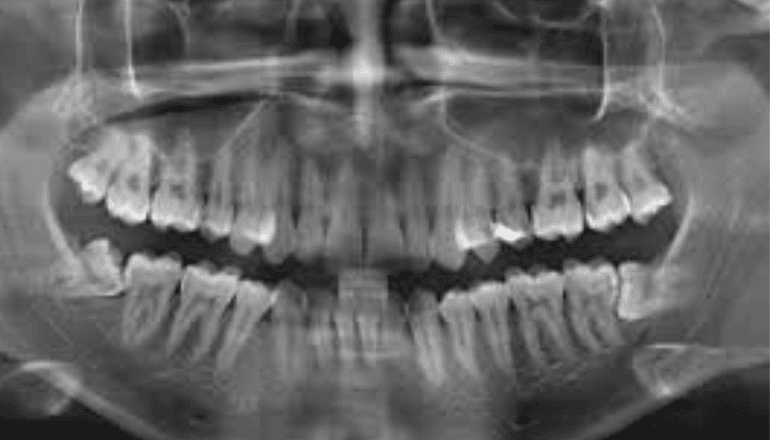

An Orthopantomogram (OPG) or panoramic dental X-ray can show a wide view of jaws, teeth and roots. It displays the nasal area, maxillary sinuses, jaw joints, teeth, upper jaw, lower jaw and surrounding bone on a single film. OPGs are used by Dentists to determine the status of wisdom teeth, to reveal cysts, tumours, bone irregularities and more.